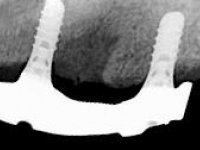

Then, the teeth were mounted in the screwed record bases and function and aesthetics were clinically evaluated. After these evaluations, the dental technician develops silicone walls that guide the fabrication of the milled bars. The precise passive fit of the bars was checked clinically and with radiographs. Then, a pick-up impression with an individualized tray was done to achieve a functional impression of the soft-tissues.